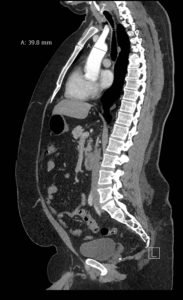

Point-of-care cardiac echocardiogram demonstrated a dilated ascending aorta (illustrated in red) measuring approximately 4 cm in the parasternal long axis (PLAX). A dilated aortic arch (illustrated in green) also measuring approximately 4 cm was appreciated using the suprasternal notch view (SSNV). A follow-up computed tomography angiogram (CTA) was performed, validating bedside ultrasound measurements.

The diagnostic criteria for dilated thoracic aneurysm is based on multiple factors including age, sex, and body size.2 An aortic root diameter of ³ 4.0 cm constitutes an ascending aortic dilation.3,4 Point-of-care cardiac and SSNV ultrasound of the thoracic aorta has been validated as an accurate study when performed by emergency physicians to identify thoracic aortic aneurysms (sensitivity of 71.4%, specificity of 100% when compared to gold standard of CTA). 5 This case is an example of the utility of rapid bedside diagnostic ultrasound, specifically the SSNV, in assessment of thoracic aneurysms.

Point-of-care cardiac echocardiography demonstrated a dilated ascending aorta. Finding a new thoracic aortic aneurysm in the setting of chest pain and hypertension is a “can’t miss” diagnosis due to the potential for rapid expansion leading to dissection and/or rupture.6 Point-of-care ultrasound utilizing the SSNV is a tool that can be used early in the evaluation of the patient that can help make quick determination of diagnostic plan and expedite initiating treatment in the emergency department.